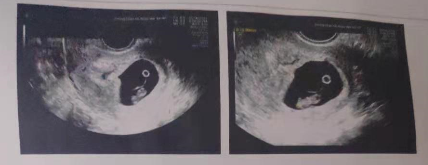

2019年5月23日,刘女士进行了冷冻胚胎移植(移植一枚优质囊胚)。术后的11天验孕——阳性,两道杠!王丝丝医生不忘叮嘱刘女士多放松身心,定期做好一、二、三超检查。